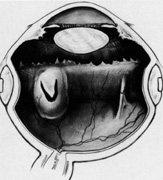

Tenon's capsule is a fascial tissue that invests both the globe and extraocular muscles. Anteriorly it fuses with conjunctiva at the limbus, and posteriorly it ends at the optic nerve sheath. Between Tenon's capsule and the sclera is the interfascial space of Tenon, or simply Tenon's space. Entering this space allows complete exposure of the scleral surface. The extraocular muscles pass through Tenon's capsule, entering Tenon's space to insert on the sclera. At the site of penetration by the individual extraocular muscles, Tenon's capsule reflects posteriorly around the muscles for 10 to 12 mm to form the muscle sheaths. The muscle sheaths are connected by the intermuscular membrane, which, in turn, is connected to the orbital wall by complex fascial arrangements. The retinal surgeon is most concerned with the extraocular muscles after they pass through Tenon's capsule (Fig. 1). At this point they do not possess a muscle sheath but, rather, are invested by episcleral tissue that fuses with the muscle. This tissue forms the falciform folds that fan out from the edges of the muscle to the overlying Tenon's capsule (Fig. 2).

Fig. 1. Anatomy of Tenon's capsule and extraocular muscles.